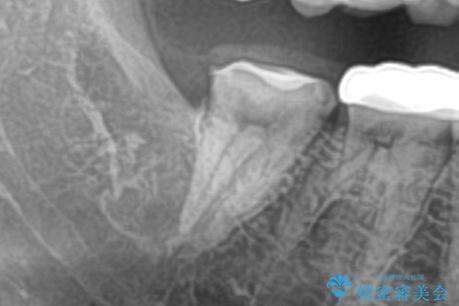

CTで神経の走行位置を確認し、抜歯術を行いました。

親知らずは生え方によっては磨きにくく、虫歯や親知らず周囲の歯肉炎による腫れや痛みを引き起こすため、抜歯をお勧めする場合があります。